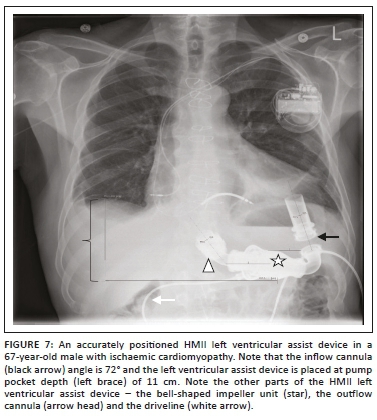

Second-generation LVADs are currently the most frequently used. Worldwide, the HeartMate II® (HMII) is the most commonly used second-generation LVAD device. The inflow and outflow cannula placements for this device are like the first-generation LVADs. The HMII can be differentiated from other LVADs as they are placed within the subdiaphragmatic preperitoneal pocket and are therefore visualised below the left hemidiaphragm on a CXR. In addition, the impeller housing unit has a characteristic 'bell-shaped' appearance, with its percutaneous single driveline supplying power to the pump exiting from the right upper quadrant of the abdomen.11 During surgical placement, the inflow cannula is oriented posteriorly towards the centre of the left ventricle (LV) cavity and connected to the pump body at roughly a 30° angle, while the outflow cannula is oriented upward to direct blood flow above the diaphragm. Malpositioned HMII pumps contribute to nearly 25% of pump thrombosis. Other factors that may contribute to pump thrombosis or failure are inflow cannula malposition and outflow cannula kink or compression.12

An acceptable CXR, to reduce the errors from patient rotation on inflow angle measurements, would be one where the sternotomy sutures are seen overlying the patient's spine or with rotations < 2 cm. The various HMII measurements that may be assessed on an AP CXR include: (1) the pump pocket depth (PPD), (2) the outflow cannula angle and (3) the inflow cannula angle. The outflow cannula is fixed to the body of the HMII with a known angle (generally >100°), and any deviation from the known angle is indicative of a CXR set-up error and rotation. It has been shown that the inflow cannula angle measurements should remain constant on serial imaging. An ideal inflow cannula angle should be >55°-65° to reduce the risk of pump thrombosis (Figure 7). Also, the inflow cannula should point to the central aspect of the left ventricle on a CXR. A deeper PPD (12 cm-14 cm) is believed to help protect against pump thrombosis. However, PPD measurements are not always precise, as the diaphragm is not a fixed structure, and the bottom of the pump on the CXR may not be the actual nadir of the pocket. Also, with time the PPD decreases by 2 cm-2.5 cm because of cranial migration of the pump, even with fixation (Figure 8).12,13 A sudden onset of pulmonary oedema could suggest LVAD failure. Other complications that may be seen on CXR include pneumothorax, pneumomediastinum, pericardial tamponade and infections. Documented sites of infection include the superficial driveline, pump pocket, the mediastinum and the internal parts of the pump for which CT is more superior than CXR for evaluation. Occasionally, because of device malfunction, the body of the HMII may be replaced without changing the outflow graft, and as a result of variations between the new and old designs, complications such as outflow bend relief detachments and kinking may be seen.5,14